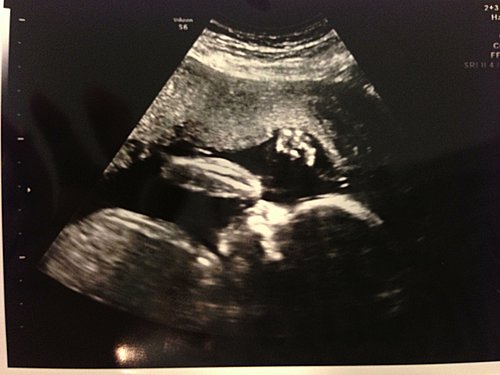

7個多月的怕羞BB

時間真是過得很快,轉一下眼懷孕已經去到第3期的最後階段了。今個月去產檢時,BB已經29週大了。 去之前幾天醫生叫我再去驗血及糖尿,糖尿仍是沒有問題,但我的貧血卻嚴重了 。醫生便要我開始吃雙倍份量的鐵補充,否則手術時有可能會大量出血啦 。 今次照BB,再用4D。上次他用手遮掩著面,所以看不到。今次也是用手遮著下爬,好像在食手指般。右腳亦提高了遮著左邊面,難度好高好像做YOGA 。不過都也可以見到3份2面孔。看... 看全文 -